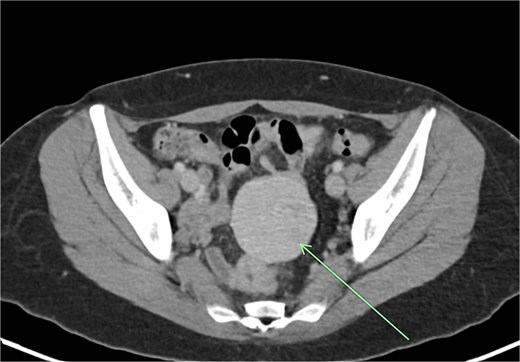

Transvaginal ultrasound demonstrated a large solid vascular mass in the left adnexa measuring 50 × 52 × 54 mm separate to the left ovary. Sonographic appearances of the uterus, endometrium, ovaries, kidneys, and bladder were reported as normal. Computed tomography (CT) demonstrated a solid rounded lesion with moderate enhancement measuring up to 55 mm. This lesion was reported as most likely to represent a broad ligament or pedunculated fibroid.

The aforementioned CT was reassessed intraoperatively together with this new information. The vascular pedicle was traced from the lesion towards the splenic vessels at the tail of the pancreas. A normal spleen was identified in the left upper quadrant (Figs 3–5). The overall impression was that this lesion represented accessory splenic tissue. The general surgery team called the patient’s next of kin, who gave consent to proceed with an excision of this wandering accessory spleen.

Long vascular pedicle leading to accessory spleen in the pelvis.